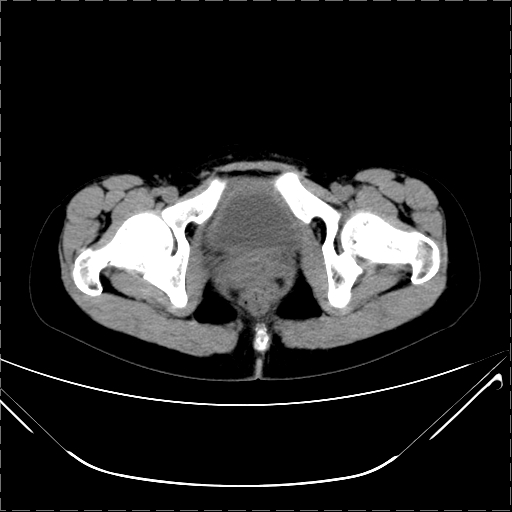

女 29岁 突然腹部疼痛1天 b超示子宫左后方肿块。月经正常。

请各位指教 该病人子宫周围云絮状高密度影是什么

影像表现复杂,膀胱上见一囊性包块,比膀胱密度高,其内有不均匀稍高密度,似与道格拉斯窝肿物无分界,病灶没有张力,因其腹平坦,推定其具有流动性,但又似见包膜,而b超没有报告这一现象。确实没见过。考虑卵巢囊肿蒂扭转并囊内出血可能。

病变主要位于道格拉斯窝,而且大体形态比较扁平且贴合子宫直肠,无明显张力及对周围脏器压迫,所以考虑为液体,而中间可见囊样病变伴环形强化,期内还可见分隔影,结合突发急性腹痛故多考虑囊腺瘤伴破裂出血。

腹腔镜术后 卵巢黄体囊肿破裂出血